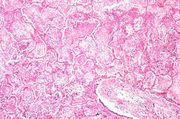

| 03:38, 19 August 2013 | IPLab3Tuberculosis2.jpg (file) | 22 KB | Seung Park | This low-power photomicrograph of a section of lung reveals multiple large nodules (1) with pale eosinophilic centers surrounded by a rim of blue-staining nuclei. In addition to the large nodules, there are several smaller nodules throughout the slide ... | 1 | |